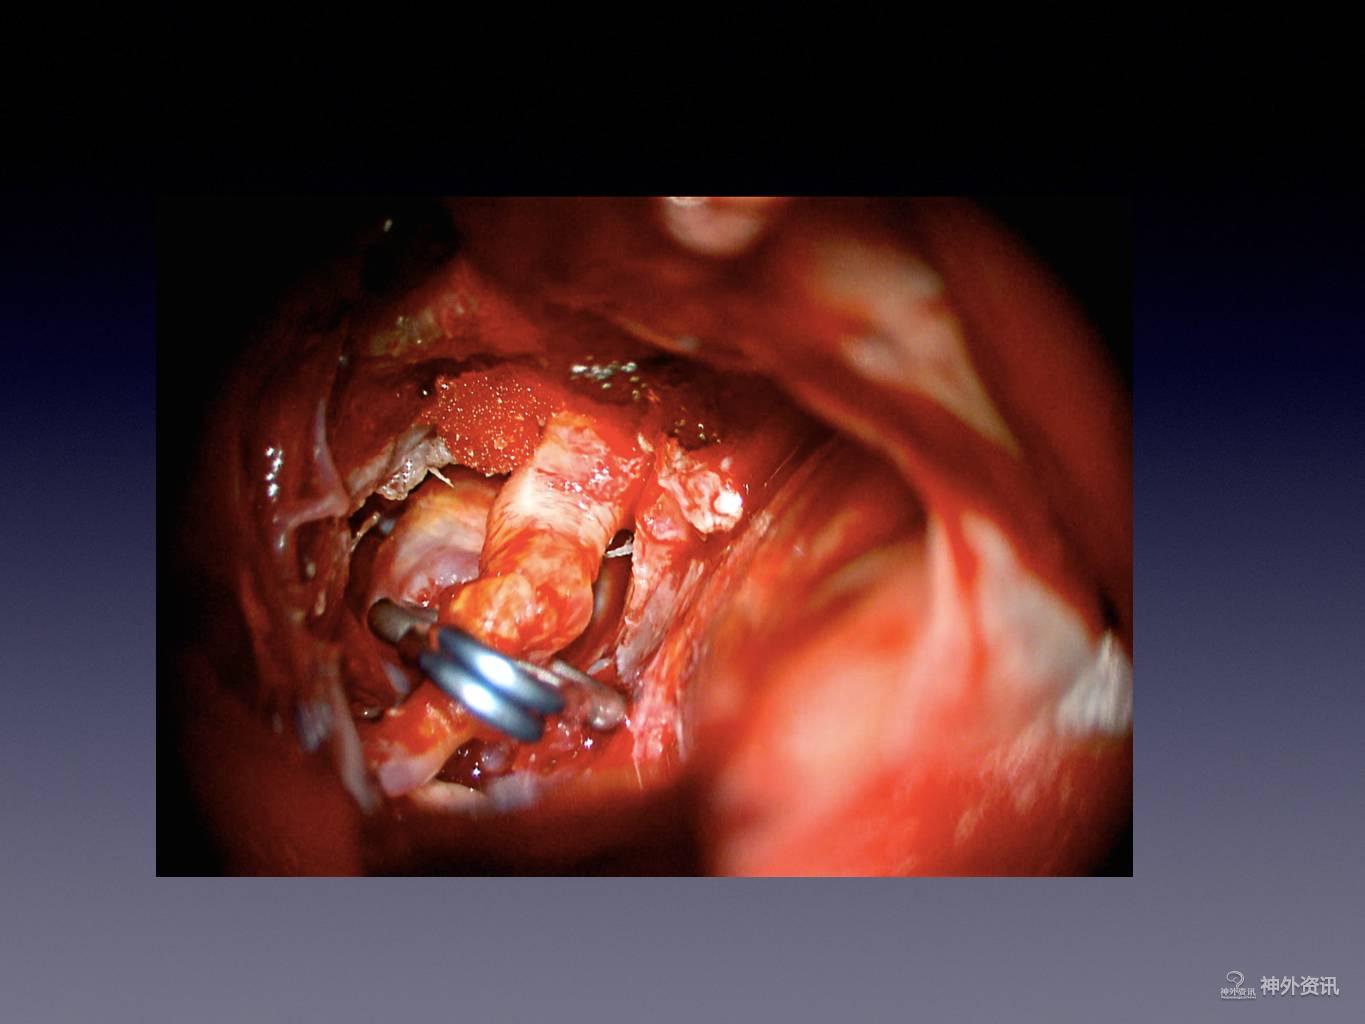

王林教授:床突旁动脉瘤夹闭手术

今天为大家分享的是《正海-妙术视界》第二十二期,由浙江大学医学院附属第二医院神经外科王林教授带来的床突旁动脉瘤夹闭手术,视频非常精彩,欢迎观看。